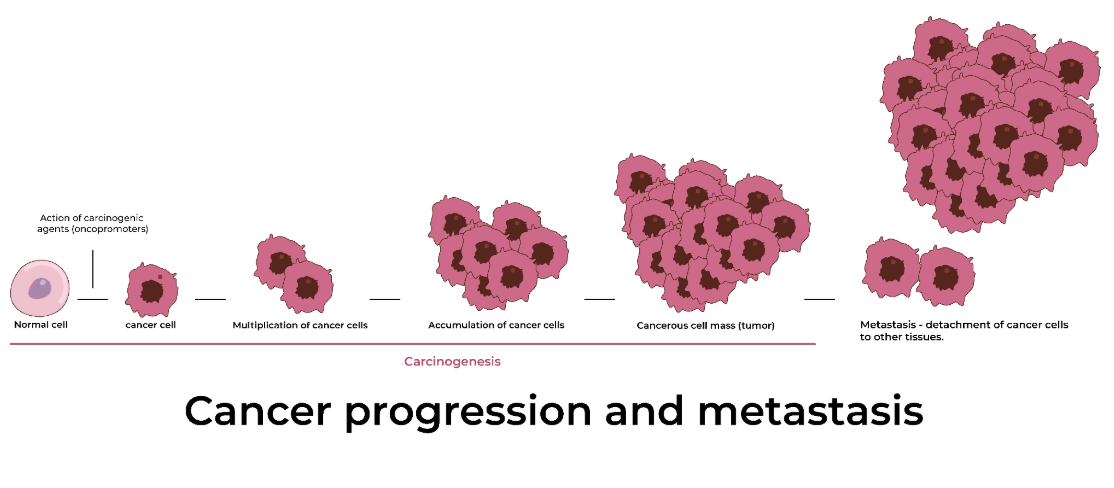

Tumor

Abnormal mass of cells that can harm tissues, organs, and systems. This can lead to cancer.

Cancer

When cells grow out of control and damage healthy organs and tissues

Metastasis

The process of cancer cells breaking away from the original (primary) tumor and establishing another (secondary) tumor elsewhere in the body